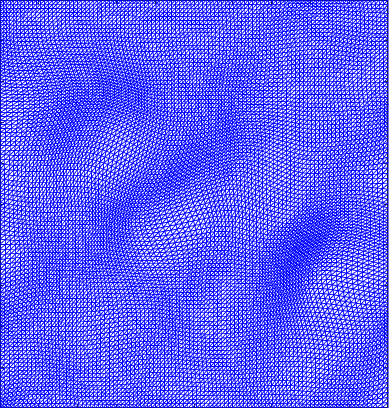

To better observe the result of our experiment, Figure 3 shows the second row of Table 2. The area bounded by the red box is the periphery of the beating heart. Figure 3(a) shows the ground truth frame. Figure 3(b) shows a frame with a perturbation combined with the normal deformation. The deformation between a frame and the reference image is computed by registration and represented by the Beltrami coefficient. Figure 3(c) shows the deformed image from the reference frame by the low rank part of the deformation. It closely resemble the ground truth frame as shown in Figure 3(a). Figure 3(d) shows the deformed image from the reference frame by the sparse part of the deformation. It demonstrates how the abnormal motion deforms the image from the reference frame. Thus, Figure 3(d) should be different from Figure 3(b), since Figure 3(b) combines both the normal and abnormal motions.

Figure 4 shows the visualisation of Figure 3 mappings in the form of grids. Let and be the Beltrami coefficients of the registration maps from the reference frame to the ground truth frame in Figure 3(a) and the perturbed frame in Figure 3(b) respectively. Figure 4(a) shows the mapping associated to Beltrami coefficient , and Fig 4(b) shows the mapping associated to BC . From Figure 4(c) and Fig 4(d), we can see that our method successfully restored the normal and abnormal deformation. Figure 4 serves as evidence that our decomposition is meaningful, in the sense that our method does not blindly return a Beltrami Descriptor with certain periodicity, but the decomposed descriptor does carry our desired information to recover the deformation to a large extent.